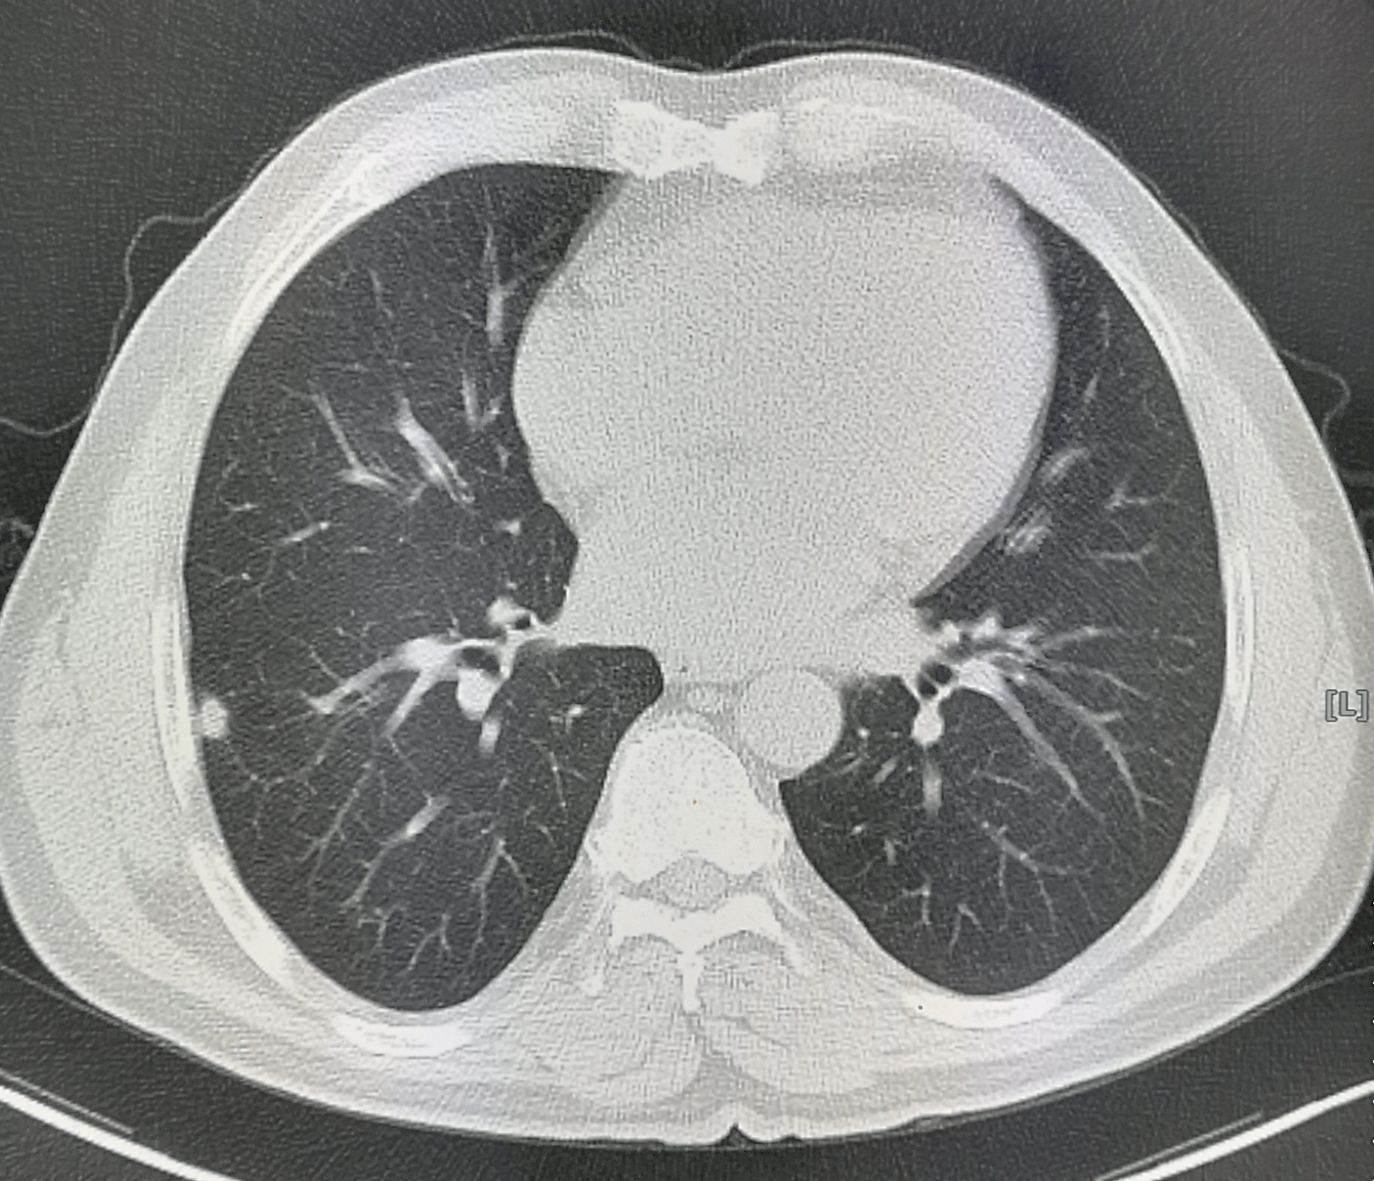

一位55岁男子,车祸发现右肺结节,9毫米:

形态不规则的实性结节,>8毫米,属于高危结节,需要进一步检查。

一般要增强CT扫描、经皮肺穿刺(结节靠近肺边缘,穿刺成功率很大),如果是恶性的,要及时手术。

在《豪大夫讲肺结节》系列文章中,我们多次讲过一个观点,靠近胸膜的实性结节,要重视!

病人拒绝了!

直到5年后,因为胸痛又来到了医院:

回顾性分析,他当初的增强CT和肺穿刺,该不该做呢?

可惜5年时间,已经错过了后悔的机会。